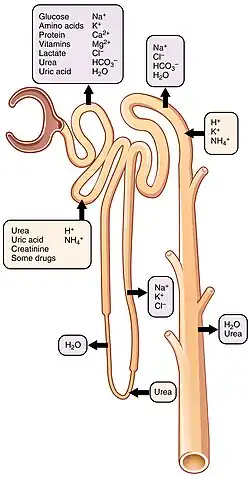

The kidney participates in the control of the volume of various body fluids, fluid osmolality, acid-base balance, various electrolyte concentrations, and removal of toxins. Filtration occurs in the glomerulus: one-fifth of the blood volume that enters the kidneys is filtered. Examples of substances reabsorbed are solute-free water, sodium, bicarbonate, glucose, and amino acids. Examples of substances secreted are hydrogen, ammonium, potassium and uric acid. The nephron is the structural and functional unit of the kidney. Each adult human kidney contains around 1 million nephrons, while a mouse kidney contains only about 12,500 nephrons. The kidneys also carry out functions independent of the nephrons. For example, they convert a precursor of vitamin D to its active form, calcitriol; and synthesize the hormones erythropoietin and renin.

The kidneys excrete a variety of waste products produced by metabolism into the urine. The microscopic structural and functional unit of the kidney is the nephron. It processes the blood supplied to it via filtration, reabsorption, secretion and excretion; the consequence of those processes is the production of urine. These include the nitrogenous wastes urea, from protein catabolism, and uric acid, from nucleic acid metabolism. The ability of mammals and some birds to concentrate wastes into a volume of urine much smaller than the volume of blood from which the wastes were extracted is dependent on an elaborate countercurrent multiplication mechanism. This requires several independent nephron characteristics to operate: a tight hairpin configuration of the tubules, water and ion permeability in the descending limb of the loop, water impermeability in the ascending loop, and active ion transport out of most of the ascending limb. In addition, passive countercurrent exchange by the vessels carrying the blood supply to the nephron is essential for enabling this function.

Reabsorption

Reabsorption is the transport of molecules from this ultrafiltrate and into the peritubular capillary network that surrounds the nephron tubules.[33] It is accomplished via selective receptors on the luminal cell membrane. Water is 55% reabsorbed in the proximal tubule. Glucose at normal plasma levels is completely reabsorbed in the proximal tubule. The mechanism for this is the Na+/glucose cotransporter. A plasma level of 350 mg/dL will fully saturate the transporters and glucose will be lost in the urine. A plasma glucose level of approximately 160 is sufficient to allow glucosuria, which is an important clinical clue to diabetes mellitus.

Amino acids are reabsorbed by sodium dependent transporters in the proximal tubule. Hartnup disease is a deficiency of the tryptophan amino acid transporter, which results in pellagra.[34]

| Location of reabsorption | Reabsorbed nutrient | Notes |

|---|---|---|

| Early proximal tubule | Glucose (100%), amino acids (100%), bicarbonate (90%), Na+ (65%), Cl− (65%), phosphate (65%) and H2O (65%) | |

| Thin descending loop of Henle | H2O |

|

| Thick ascending loop of Henle | Na+ (10–20%), K+, Cl−; indirectly induces para cellular reabsorption of Mg2+, Ca2+ |

|

| Early distal convoluted tubule | Na+, Cl− |

|

| Collecting tubules | Na+(3–5%), H2O |

|

Secretion

Secretion is the reverse of reabsorption: molecules are transported from the peritubular capillary through the interstitial fluid, then through the renal tubular cell and into the ultrafiltrate.